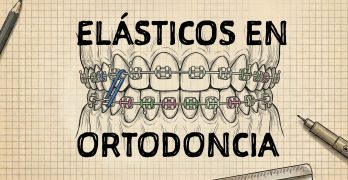

Todo lo que el Ortodoncista necesita saber sobre elásticos

Este artículo llamado Elastics in Orthodontics: A Comprehensive Review y publicado en el International Journal of … [Leer más...] acerca de Todo lo que el Ortodoncista necesita saber sobre elásticos